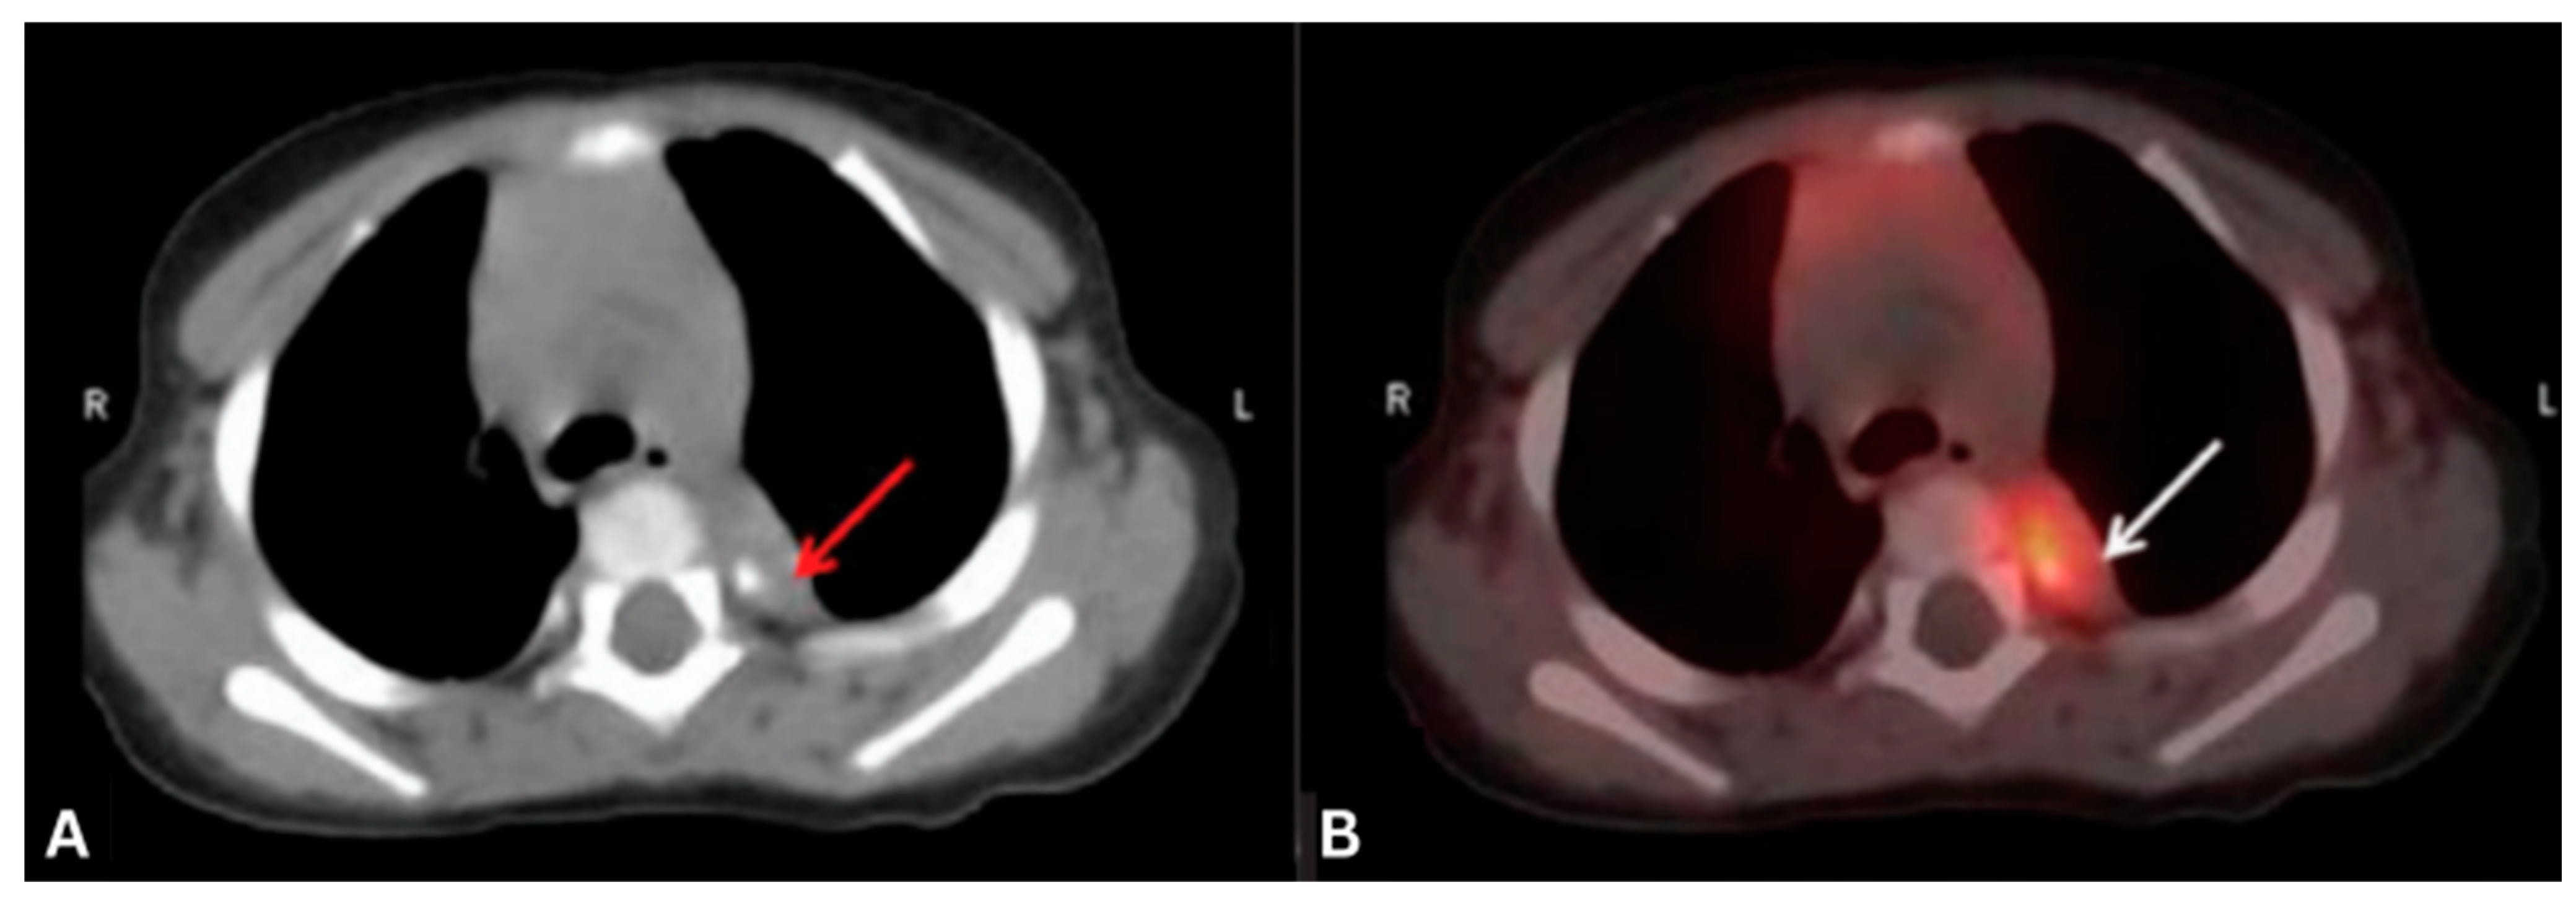

- Chen, G.; Fu, Z.; Chen, X.; Li, Q. Lambert-Eaton Myasthenic Syndrome Associated with Extrapulmonary Small Cell Cancer Detected by 18F-FDG PET/CT. Clin. Nucl. Med. 2018, 43, 697–698. [Google Scholar] [CrossRef]

- Zhang, K.; Liu, W.; Li, Y.; Zhang, K.; Gao, X.; Wang, J. Mediastinal Small Cell Cancer Associated with Lambert-Eaton Myasthenic Syndrome: A Case Report. Exp. Ther. Med. 2015, 10, 117–120. [Google Scholar] [CrossRef][Green Version]